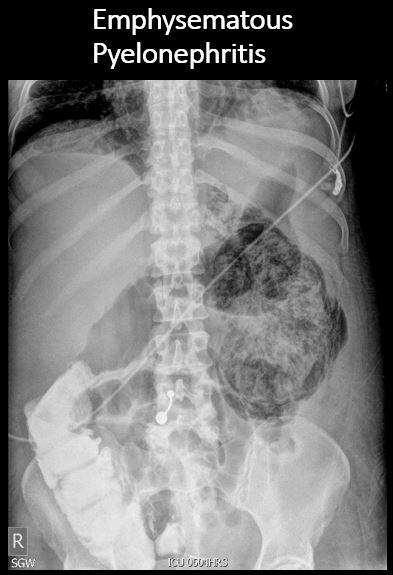

There is renal or ureteral associated air. |

No | NA |